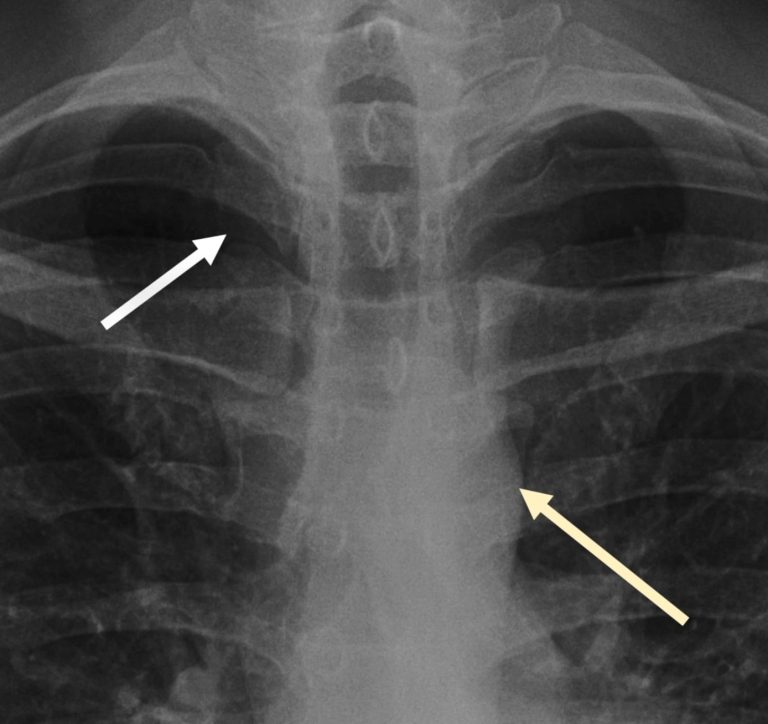

I do not consider a chest X‑ray fully reviewed until I have zoomed right in on both apices and that’s mainly because a pneumothorax can be very subtle unless you magnify the film. A pneumothorax represents gas within the pleural space – remember the pleura has two layers the visceral (inner) and parietal pleura (outer).

Pneumothorax represents gas within the pleural space, between the inner visceral and outer parietal pleura.

The two cardinal signs to look for are, firstly, a lucent black area of lung without visible vascular markings and, secondly, a thin white pleural line representing the visceral pleura separating from the parietal pleura. Compare side to side: if one apex lacks markings where the other has them, this should ring alarm bells. Bullae from emphysema can mimic a lucent pneumothorax, but these tend to be round and do not display a sharp pleural line paralleling the chest wall.

Here in this case we have the two cardinal signs of pneumothorax: one, a white pleural line (yellow arrow) and two lucency without lung markings outside of this.